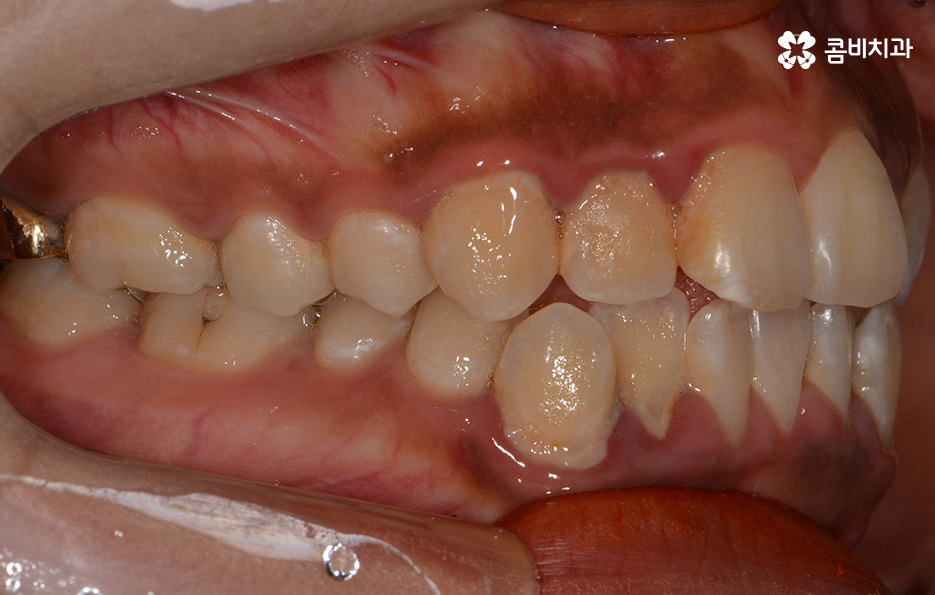

옆모습으로 볼때 돌출된 치아로 인한 돌출입 상태

클리피씨교정의 경우 치료 기간이 단축된다는 점에서 관심을 갖는 분들이

많습니다. 하지만 치열, 교합 상태, 발치 유무 등을 감안하여

치료 계획을 세우기 때문에 개개인마다 치료 기간이 다를 수 있습니다.